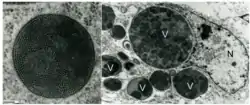

PBFD is caused by the Beak and feather disease virus (BFDV), a circular or icosahedral, 14–16 nm diameter, single-stranded circular DNA, non-enveloped virus with a genome size of between 1992 and 2018 nucleotides. It encodes seven open reading frames—three in the virion strand and four in the complementary strand.[6] The open reading frames have some homology to porcine circovirus (family Circoviridae), subterranean clover stunt virus and faba bean necrotic yellows virus (both family Nanoviridae).

The beak and feather disease virus (BFDV) is currently considered a member of the family Circoviridae. Like other circoviruses, BFDV possesses a small, circular single-stranded DNA (ssDNA) genome (approximately 2.0 kb in length) that is encapsidated into a non-enveloped, spherical icosahedral virion.[8] In order to replicate its genome, BFDV needs to invade the nucleus to access the transcriptional machinery of the host cell. The replication of BFDV is known to occur in numerous tissues, including skin, liver, gastrointestinal tract, and bursa of Fabricius;[9][10] while the capsid antigen of BFDV is found in the spleen, thymus, thyroid, parathyroid and bone marrow.[11] However, the distinction between viral entry and replication in a host cell remains unclear in the absence of confirmation in suitable cell culture. Viral attachment and entry into host cells may not necessarily lead to viral replication, and consequently not all cells containing viral particles may contribute to the disease progression. However, it is thought that the BFDV encodes proteins that actively transport the viral genome into the nucleus, as well as factors that direct the precursor DNA exit to the cytoplasm, where it causes large globular intracytoplasmic paracrystalline arrays.[8]

The BFDV genome is bi-directionally transcribed and encodes at least two major proteins: a replication initiation protein (rep) expressed from the virion strand and a capsid protein (cap) expressed from the complementary strand. A recent study conducted by Sarker et al. used a combination of X-ray crystallography, cryo-electron microscopy and atomic force microscopy to investigate the functionality of cap and its interaction with a range of host and viral proteins. They confirmed that the cap protein forms virus-like particles (VLPs) of ~17 nm (mature form) and a smaller assembly of ~10 nm (immature form).[8] Furthermore, this study demonstrated that assembly of these two VLPs is regulated by single-stranded DNA (ssDNA), and that they provide a structural basis of capsid assembly around single-stranded DNA.[8]